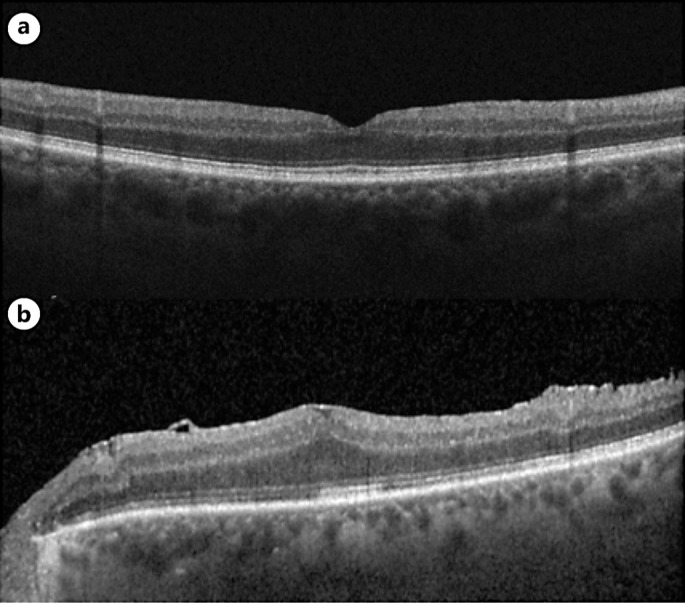

Case presentation: A 67-year-old man with no significant past medical history was referred to our retina clinic with a diagnosis of foveal hypoplasia. He had been experiencing significant vision loss for more than 1 year. OCT demonstrated absence of the foveal depression in both eyes. A subtle ERM was identified in the left eye OCT, but the presence of an ERM in the right eye OCT was equivocal. As such, it was unclear whether flattening of the fovea was attributable to hypoplasia or ERM based on OCT alone. This prompted further investigation with OCTA, which showed the presence of the FAZ in both eyes. The diagnosis of stage 2 ERM OU was made based on OCTA findings. The patient underwent cataract extraction with intraocular lens implantation, pars plana vitrectomy, and ERM peel, which resulted in improvement of visual symptoms and visual acuity. Follow-up OCT showed normalization of the foveal pit in the right eye greater than the left eye.

Conclusion: This case demonstrates the importance of utilization of OCTA in differentiating true foveal hypoplasia from this foveal "pseudo-hypoplasia" exhibited by our patient.